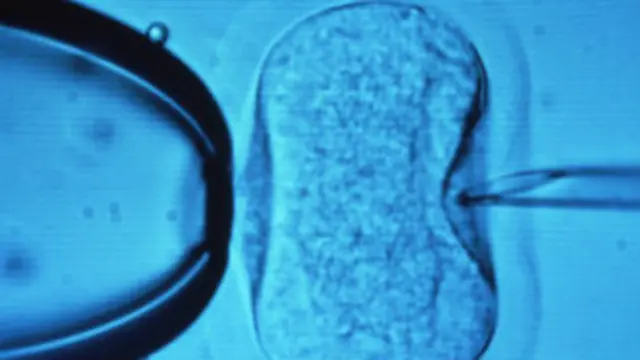

न्यूकैसल में विकसित तकनीक में आईवीएफ़ के आधुनिक संस्करण का उपयोग दानदाता महिला के माइटोकॉन्ड्रिया को माता-पिता के डीएनए से मिलाने में किया जाता है.